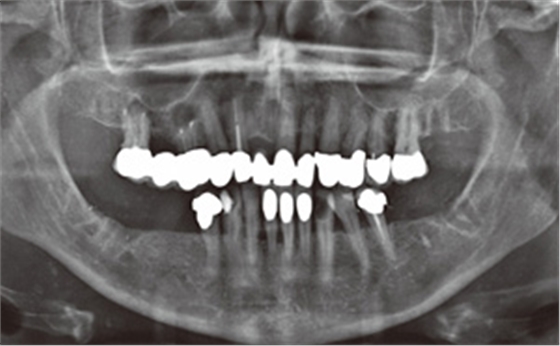

由于在2013 年10 月15 日的X 線檢查時(shí)已經(jīng)看到根管充填不足和根尖周骨質(zhì)溶解,因此在2013 年10 月21 日為16 和14 號牙齒行根尖切除術(shù)及倒充治療。另外,拔除27和37 號牙齒。隨后,拍攝了曲面斷層全景片(圖8)。修復(fù)性治療因33 和43 號牙齒計(jì)劃進(jìn)行全冠修復(fù),2013 年11 月5日由家庭牙醫(yī)進(jìn)行充填治療。此外,對根管充填不足的16和14 號牙齒重新根充,以用于上頜修復(fù)體的基牙。修復(fù)治療最早可在重新評估后再進(jìn)行,首先需要改善和穩(wěn)定牙周狀況。

圖8:2013 年10 月21 日術(shù)后曲面斷層全景X 線片(根尖切除和牙齒拔除)。